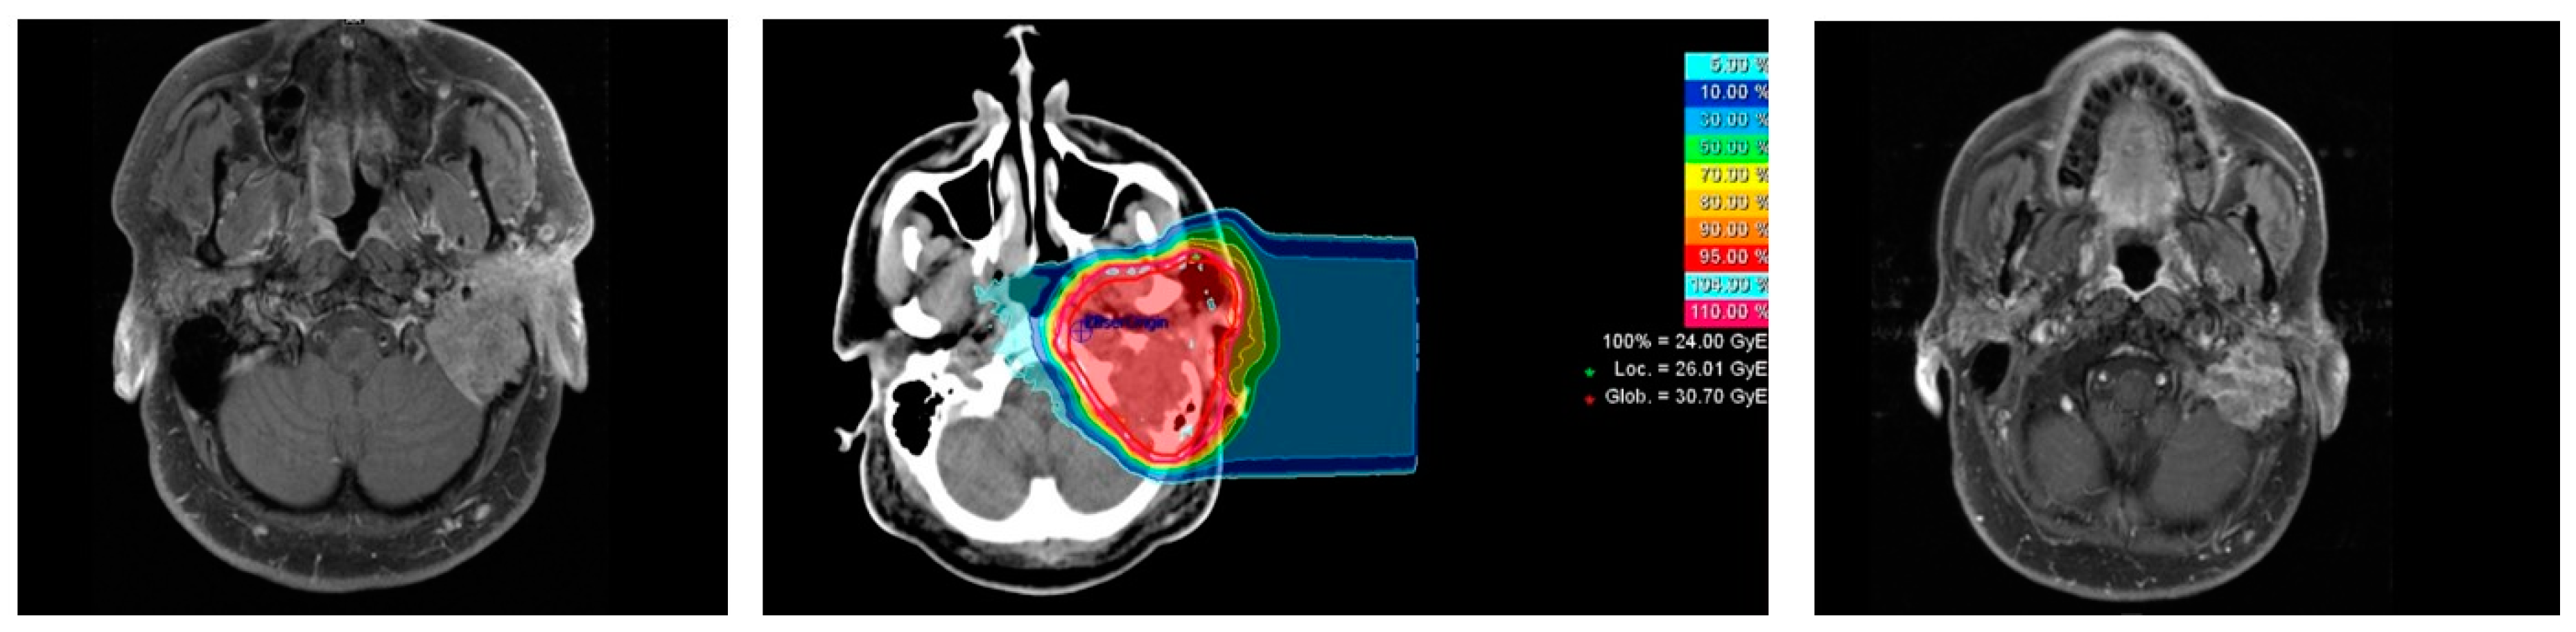

2.2. Treatment Characteristics

4.2. Radiotherapy

| Carbon Ion Radiotherapy | metric |

| Median GTV in cm3 (range) * | 37 (15–182) |

| Median CTV1 in cm3 (range) | 106 (32–594) |

| Median prescribed single dose in Gy RBE-weighted dose (range) | 3 (3–3) |

| Median prescribed total dose in Gy RBE-weighted dose (range) | 24 (18–24) |

| Number of beams (n) | |

| 1 | 7 |

| 2 | 8 |